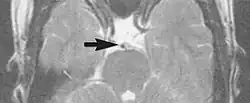

Fig. 8. Gibbs artifact (T1 sagittal study of the brain).[1]

Gibbs artifacts or Gibbs ringing artifacts, also known as truncation artifacts are caused by the under-sampling of high spatial frequencies at sharp boundaries in the image.[5][6] Lack of appropriate high-frequency components leads to an oscillation at a sharp transition known as a ringing artifact. It appears as multiple, regularly spaced parallel bands of alternating bright and dark signal that slowly fade with distance (Fig. 8). Ringing artifacts are more prominent in smaller digital matrix sizes.[1] Methods employed to correct Gibbs artifact include filtering the k-space data prior to Fourier transform, increasing the matrix size for a given field of view, the Gegenbauer reconstruction and Bayesian approach.[1]